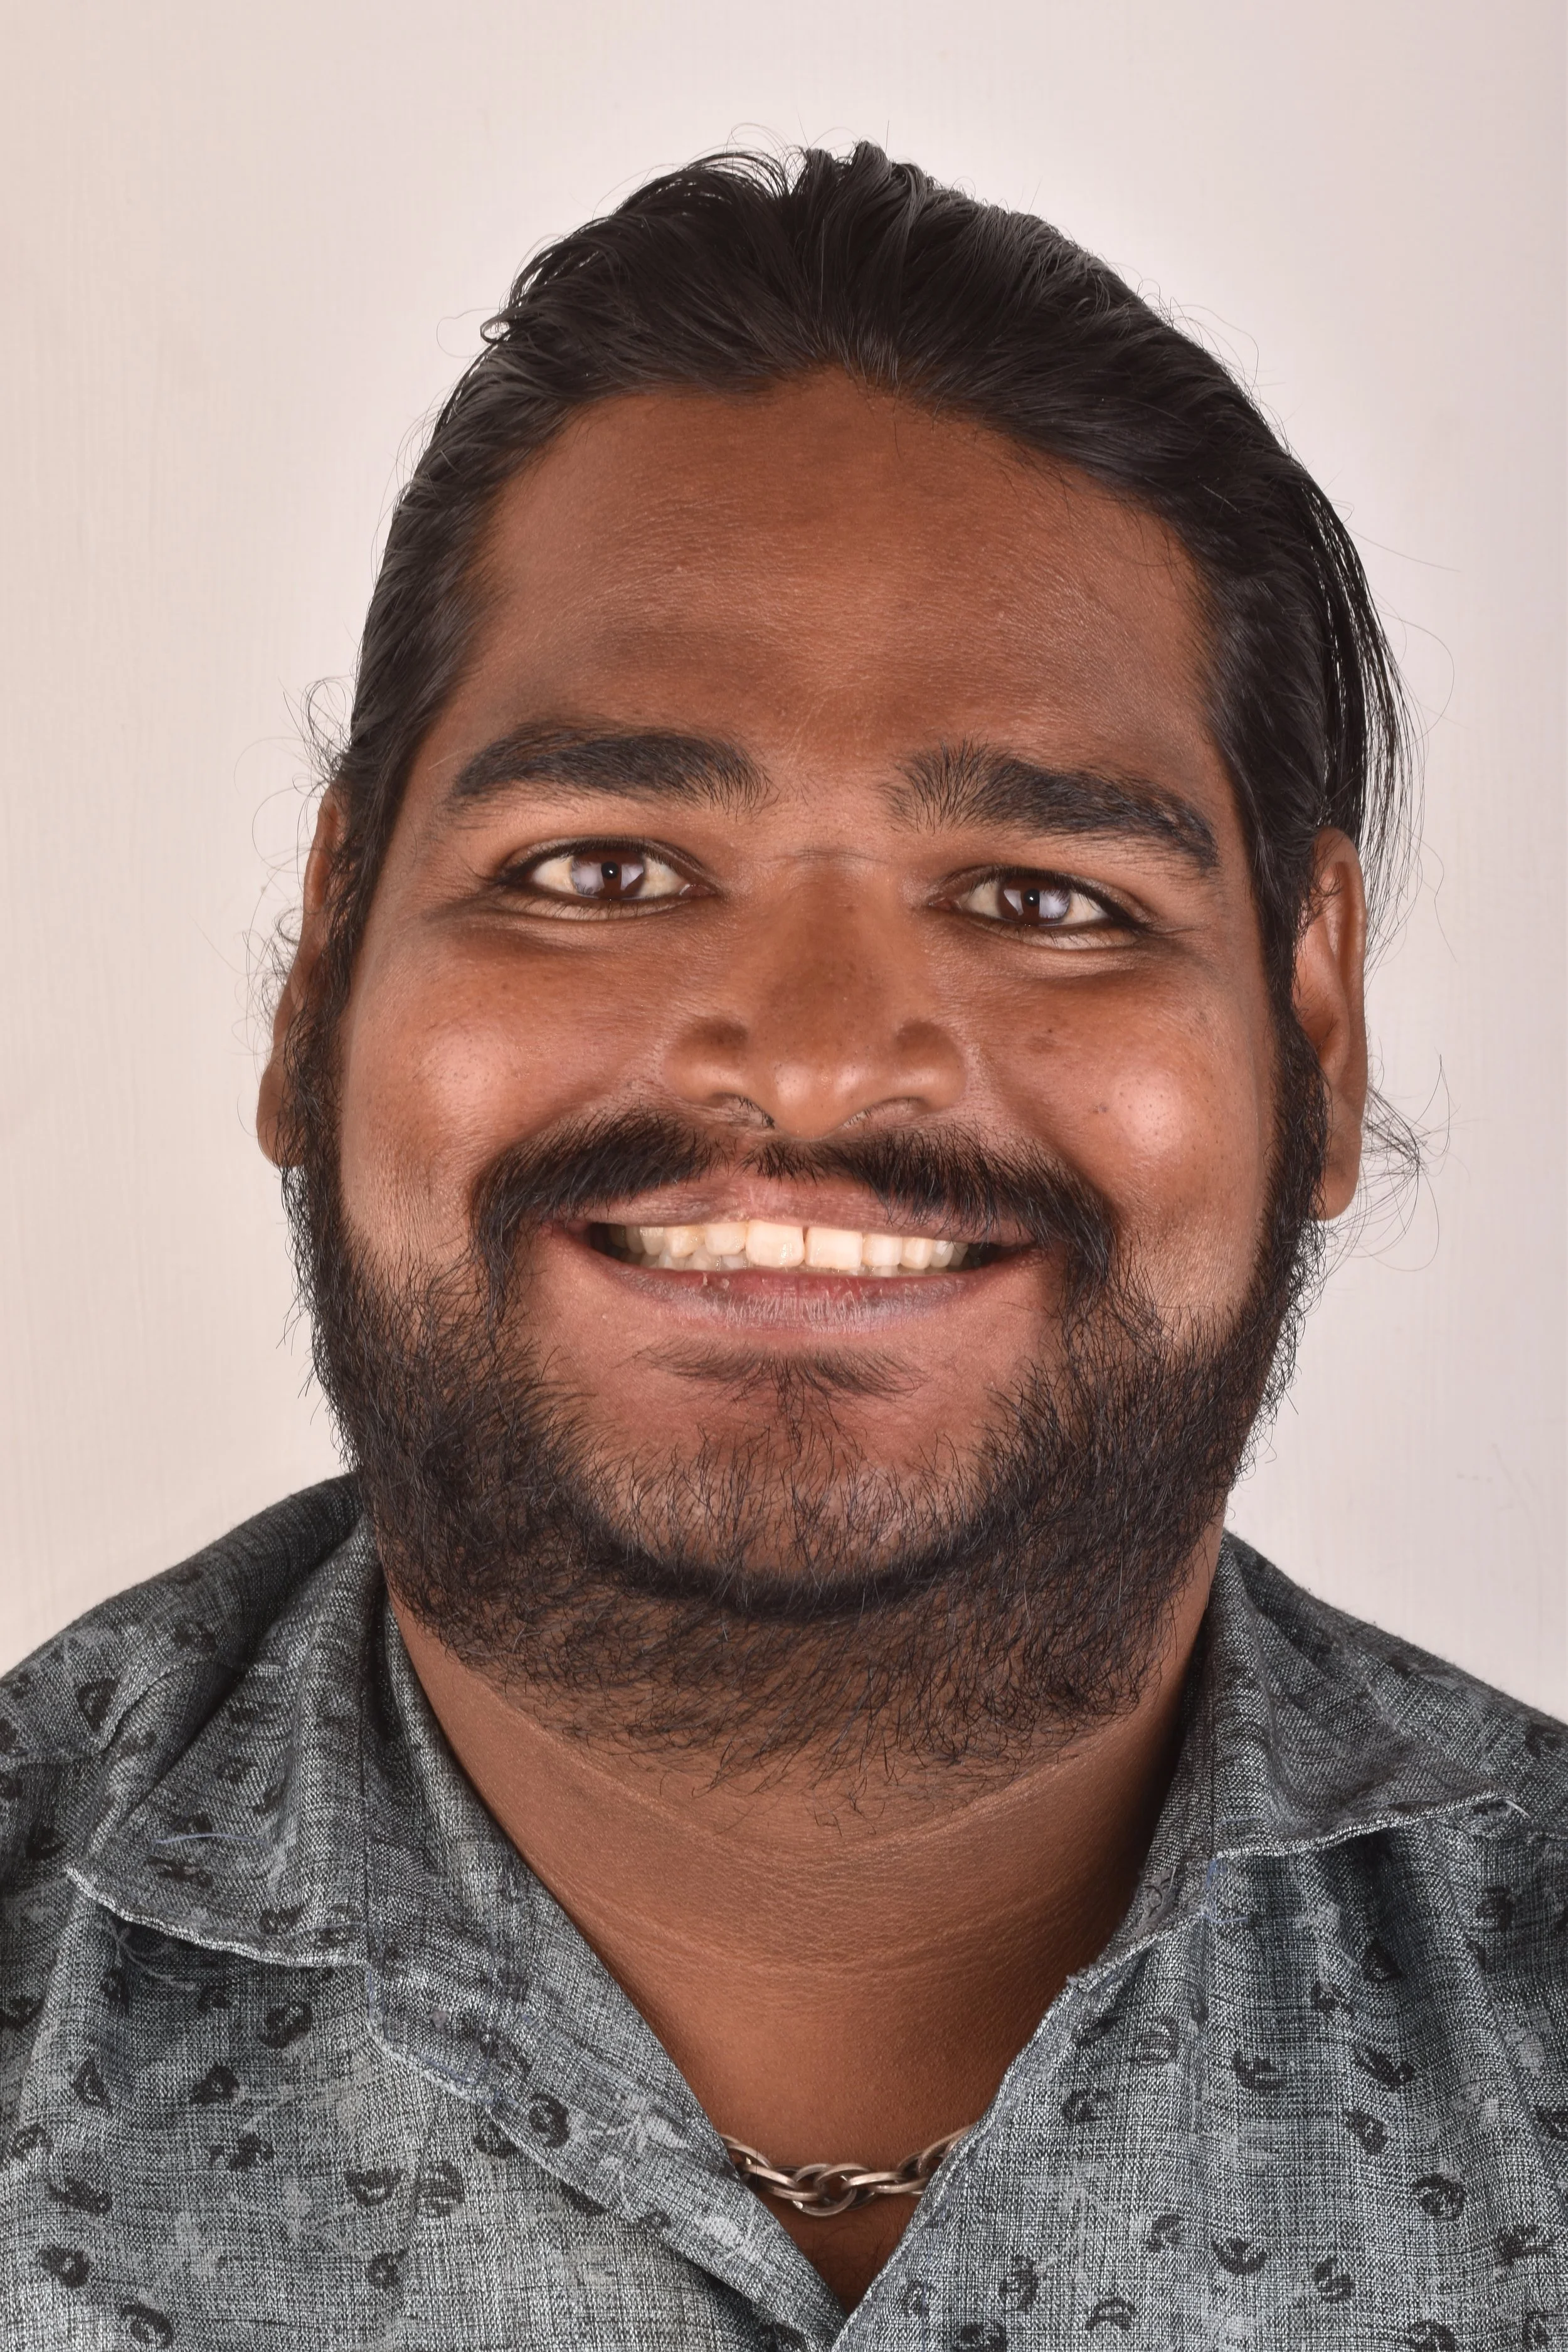

DISTALIZATION OF ENTIRE DENTITION WITH MINI-SCREWS ASSISSTED BY ESTHETIC SMILE MAKEOVER

DISTALIZATION OF ENTIRE DENTITION WITH MINI-SCREWS ASSISSTED BY ESTHETIC SMILE MAKEOVER